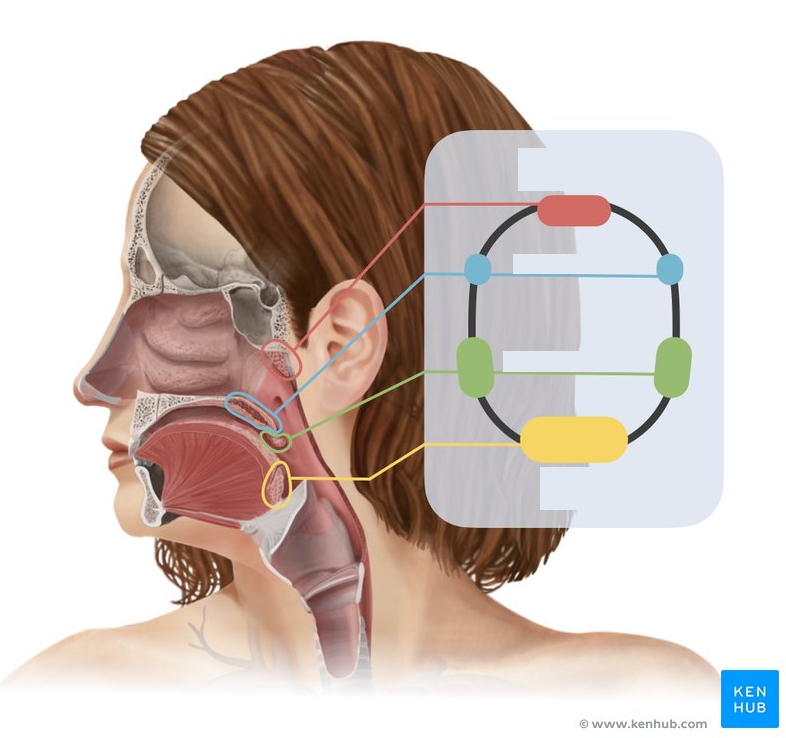

Nasopharynx

yellow highlight

Oropharynx

green highlight

Laryngopharynx

blue highlight

Entrance to auditory tube

Parotid gland

Parotid duct

Submandibular gland

Submandibular ducts

Sublingual gland

Sublingual ducts